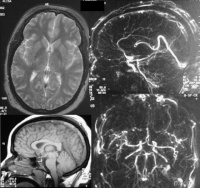

颅内压是指颅腔内容物对颅腔壁产生的压力,是由液体静力压和血管动压两因素组成。由于颅腔总容积相对固定,颅内压保待相对稳定。正常人平卧位颅内压约为l.33kPa(10mmHg)。当脑组织肿

胀、颅内占位性病变或脑背液分泌过多、吸收障碍、循环受阻或脑血流灌注过多导致颅内压持续保待在2.0kPa(l5mmHg)以上时称颅内高压(inreacranial hypertension)。

(3)脑血管造影、CT和磁共振等可间接诊断颅内高压。